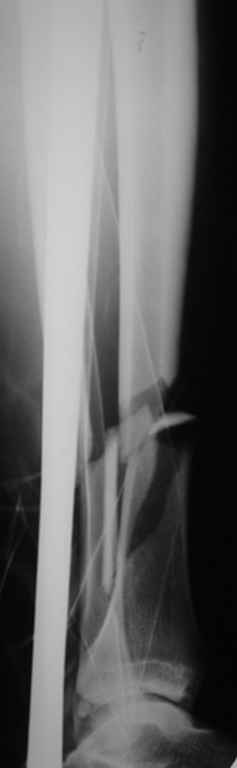

На голени что-то сделать с отломком вынуждает угроза перфорация кожи, перекрытие отломком входа в канал. Не всегда надо делать разрез, можно и шилом чрескожно фрагмент сдвинуть. Наверно, еще и повреждение сосудистого пучка, когда "виновник" прямо поперек перерезанной артерии и лежит - такое не каждый за всю свою профессиональную жизнь

То есть в представленных ситуациях при штифтовании ни на бедре, ни на голени не нужно делать ни открытую, ни закрытую (с помощью шильев,

спиц, еще каких-то "джойстиков") репозицию. Все, что нужно - восстановить ось, длину и ротацию.

Перелом большеберцовой кости почти околосуставный, могут потребоваться дополнительные меры для восстановления оси (отклоняющие спицы или винты), и запирающих винтов в дистальный отломок желательно побольше. Задний край не сломан ли там, не разобрал по этим снимкам.

>Сами собираемся оперировать голень и думаем, что без "открытия" места перелома не обойтись.

"Открытие" "открытию" рознь. Мне видится такая последовательность действий: попытаться установить проводник закрыто на вытяжении или дистракторе. Если прошел -рассверлиться, если нет поправить направление проводника через разрез такой величины, чтобы можно это было сделать но не более того.Если осколок, стремящийся в канал свободен от мягких тканей - удалить его. Удаляли вываливающиеся отломки "перстневидной" формы по более представленного, тем не менее сращение наступало. Если удастся все провести закрыто, манипуляции с отломком нужны, если он будет стремиться перфорировать кожу.Бывает, что для этого не обязательно открываться, просто подтолкнуть осколок через кожу или (цитата:))шилом.